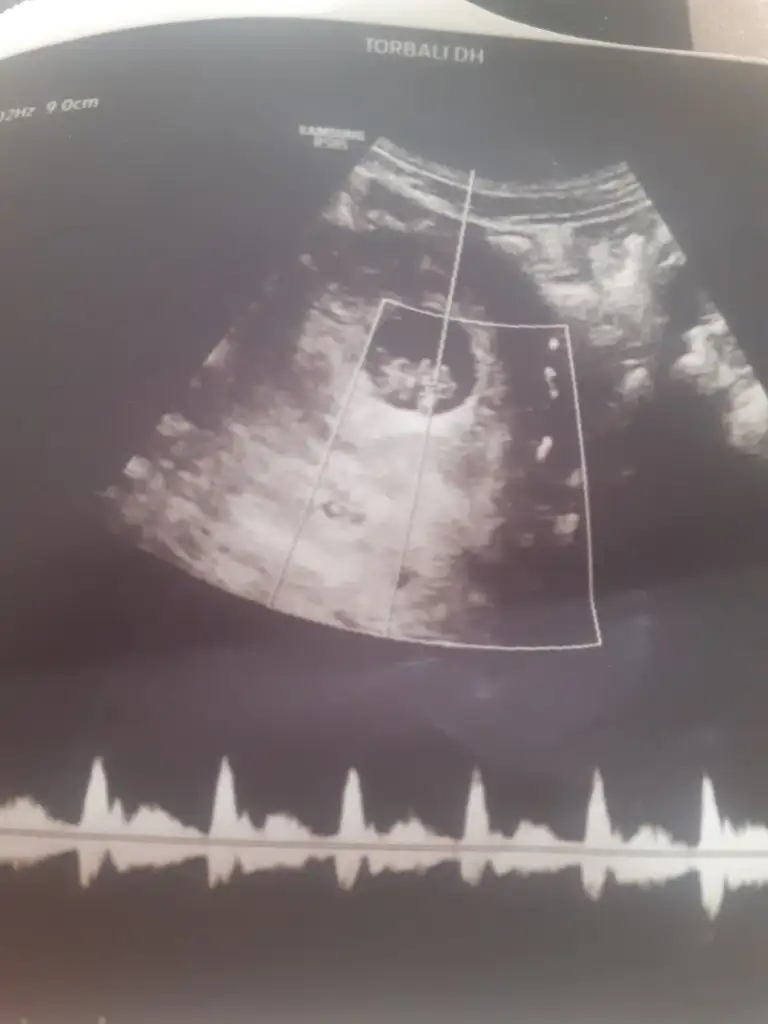

Merhaba banada tahminde bulunurmusun karından ve burda 7 ve 12 haftalıkSelam Kızlarbir çok kişi gruplardan beni bilir. Yine yetiştim imdatlara

kuzum kız gibi duruyorMerhaba banada tahminde bulunurmusun karından ve burda 7 ve 12 haftalık

kuzum karından mı?Banada bakarmisiniz lütfenn

11+4 ama ultrasonda 12+4 cıktı karından bizede tahmin yürütürmüsünüz